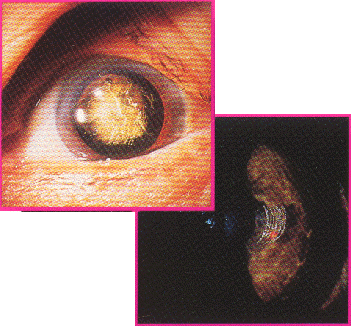

ISL 2000 / ISL 4000Picosecond lasers made possible precise cuts underneath the surface of the cornea.

Cataract Fragmentation and Intrastromal Incisions.

The ISL 2000 Model. A variety of patterns, their dimensions and depths could be programmed by the physisian.